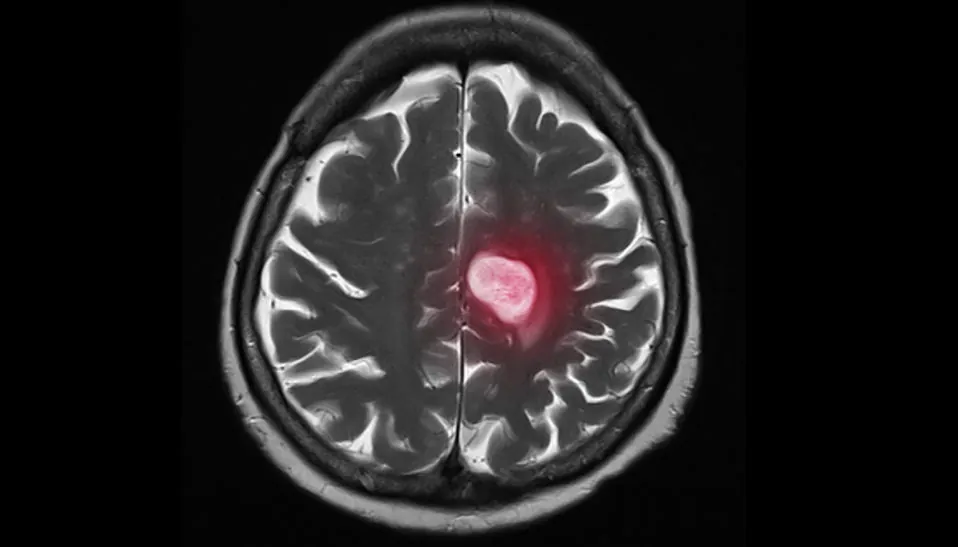

The Hallmarks of Metastasis

It is the one word you do not want to hear in a cancer diagnosis: metastasis. It represents the figurative death-knell; once a cancer has spread to other parts of the body, survival rates plummet and what treatments do exist switch from curative to palliative. The dividing line metastatic cancer…...